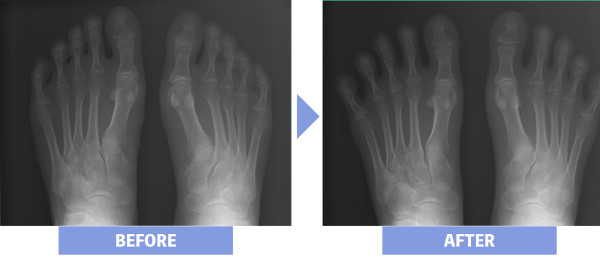

2. Bunion

Bunion gây ra cảm giác đau và tê ở phần bên trong của ngón cái và phía sau ngón tay cái. Cơn đau trở nên nghiêm trọng hơn khi ngón cái chạm vào giày hoặc bị áp lực từ các vật nặng.